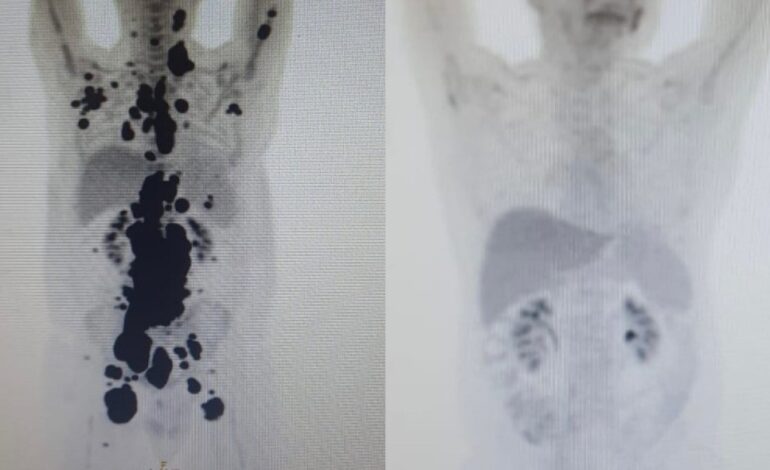

Diabetes: concentrações levemente elevadas de duas proteínas na corrente sanguínea são um sinal de mudanças na estrutura e no funcionamento do coração — Foto: Wikimedia